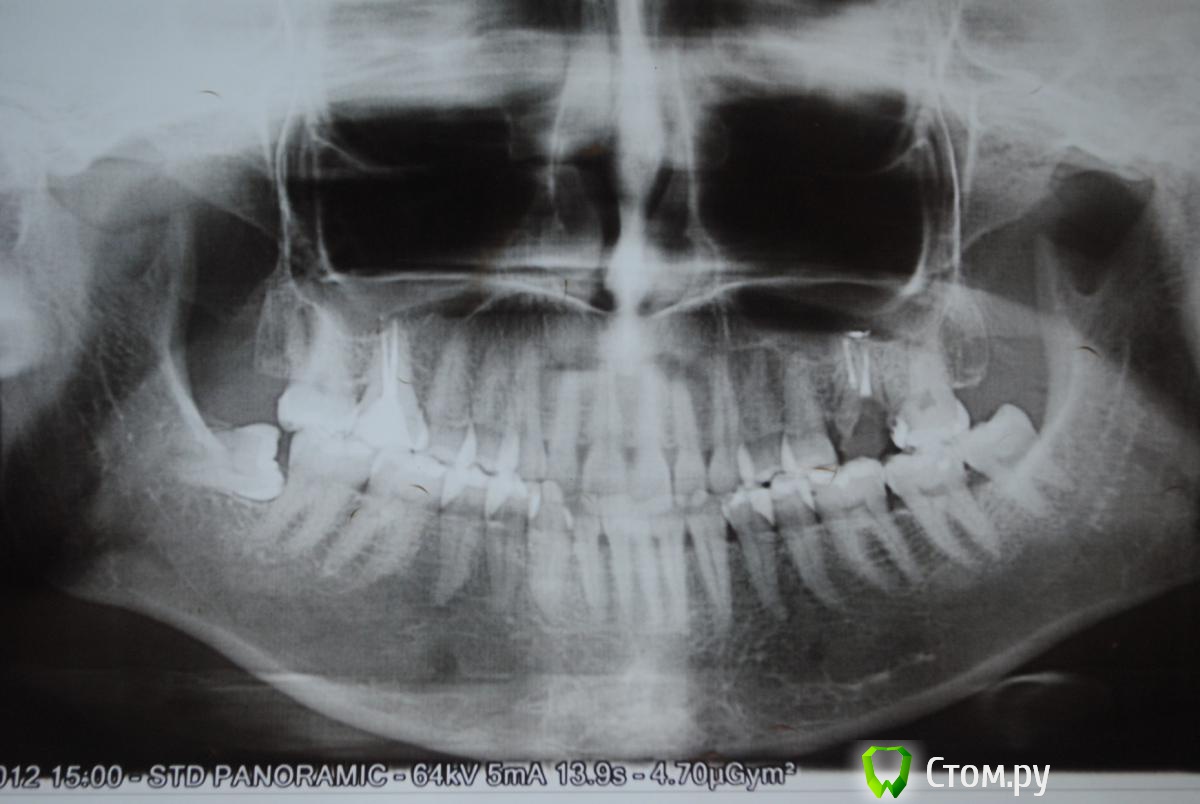

Irson Опубликовано 10 ноября, 2014 Поделиться Опубликовано 10 ноября, 2014 Уважаемые доктора, здравствуйте! Прошу вашего совета. Неделю назад у меня появилась боль и припухлость десны в области ретинированной 8-ки снизу, образовался гнойник. Боль умеренная, в области нарыва, немного при глотании. Поласкала содой, гнойник прорвался, но через неделю образовался снова. Сделала снимок. При осмотре мне назначили антибиотикотерапию цифран 3 раза в день по 500 мг - 3 дня и найз по 1 т. 3 раза в день - 3 дня. Промыли хлоргексидином и положили лекарство(названия не знаю). Сказали, что зуб нужно удалять. Скажите пожалуйста, как срочно нужно удалить зуб? Могу ли я подождать три недели(так как у меня очень важная поездка) или это опасно и могут быть осложнения? Посоветуйте пожалуйста место в Москве, где лучше всего удаляют такие зубы? Очень боюсь. Заранее спасибо за ответ. Снимки: панорамный 2 года назад и прицельный сегодня. Ссылка на комментарий

SDC Опубликовано 10 ноября, 2014 Поделиться Опубликовано 10 ноября, 2014 (изменено) Если 3 недели до поездки, то сейчас лучшее время для удаления.Удаляя зуб за 2-3 недели до отъезда, Вы имеет в запасе время для реабилитации и страхуетесь от осложнений в поездке.Справедливости ради, судя по представленному снимку, ничего серьезного не произойдет и через 2, и через 3, и через 6 недель. )) Для хорошей очистки десневого кармана в обл. 48 зуба и снижения риска обострения до минимума нужен ирригатор.По поводу удаления не беспокойтесь, зуб из разряда обычных, хирург с минимальным опытом способен быстро его удалить. Изменено 10 ноября, 2014 пользователем SDC 1 Ссылка на комментарий